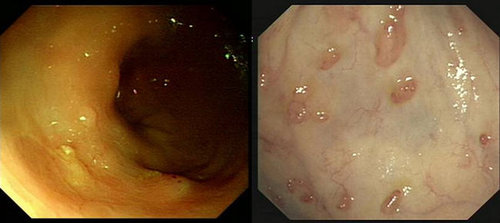

克罗恩病

克罗恩病是一种消化道的慢性、反复发作和非特异性的透壁性炎症, 病变呈节段性分布, 可累及消化道任何部位,其中以末端回肠最为常见,结肠和肛门病变也较多。

克罗恩病可累及全消化道,根据所累及的范围,可分为小肠型(30% ~ 40%)、小肠及结肠型(40% ~ 55%)、结肠型(15% ~ 25%)。累及小肠者,回盲部受侵犯的达90%以上。

按照临床表现的特点,又可分为梗阻型和成瘘型。内镜下可见跳跃性病变、裂隙样溃疡、狭窄等。内镜下粘膜活检往往不能得到充分的病理诊断依据,但有时可发现肉芽肿等病变。

结肠克罗恩病

克罗恩病中,局限于结肠的约占1/4。一般地,结肠克罗恩病不累及直肠,病变之间粘膜正常(跳跃性病变)、溃疡呈裂隙样、粘膜可呈铺路石样。

10 ~ 15%的病例在诊断为克罗恩病后的一年内被重新诊断为溃疡性结肠炎。对于不能确定诊断的局限于结肠的炎性肠病可考虑未定型结肠炎(indeterminate colitis)的诊断,但该诊断不宜滥用。